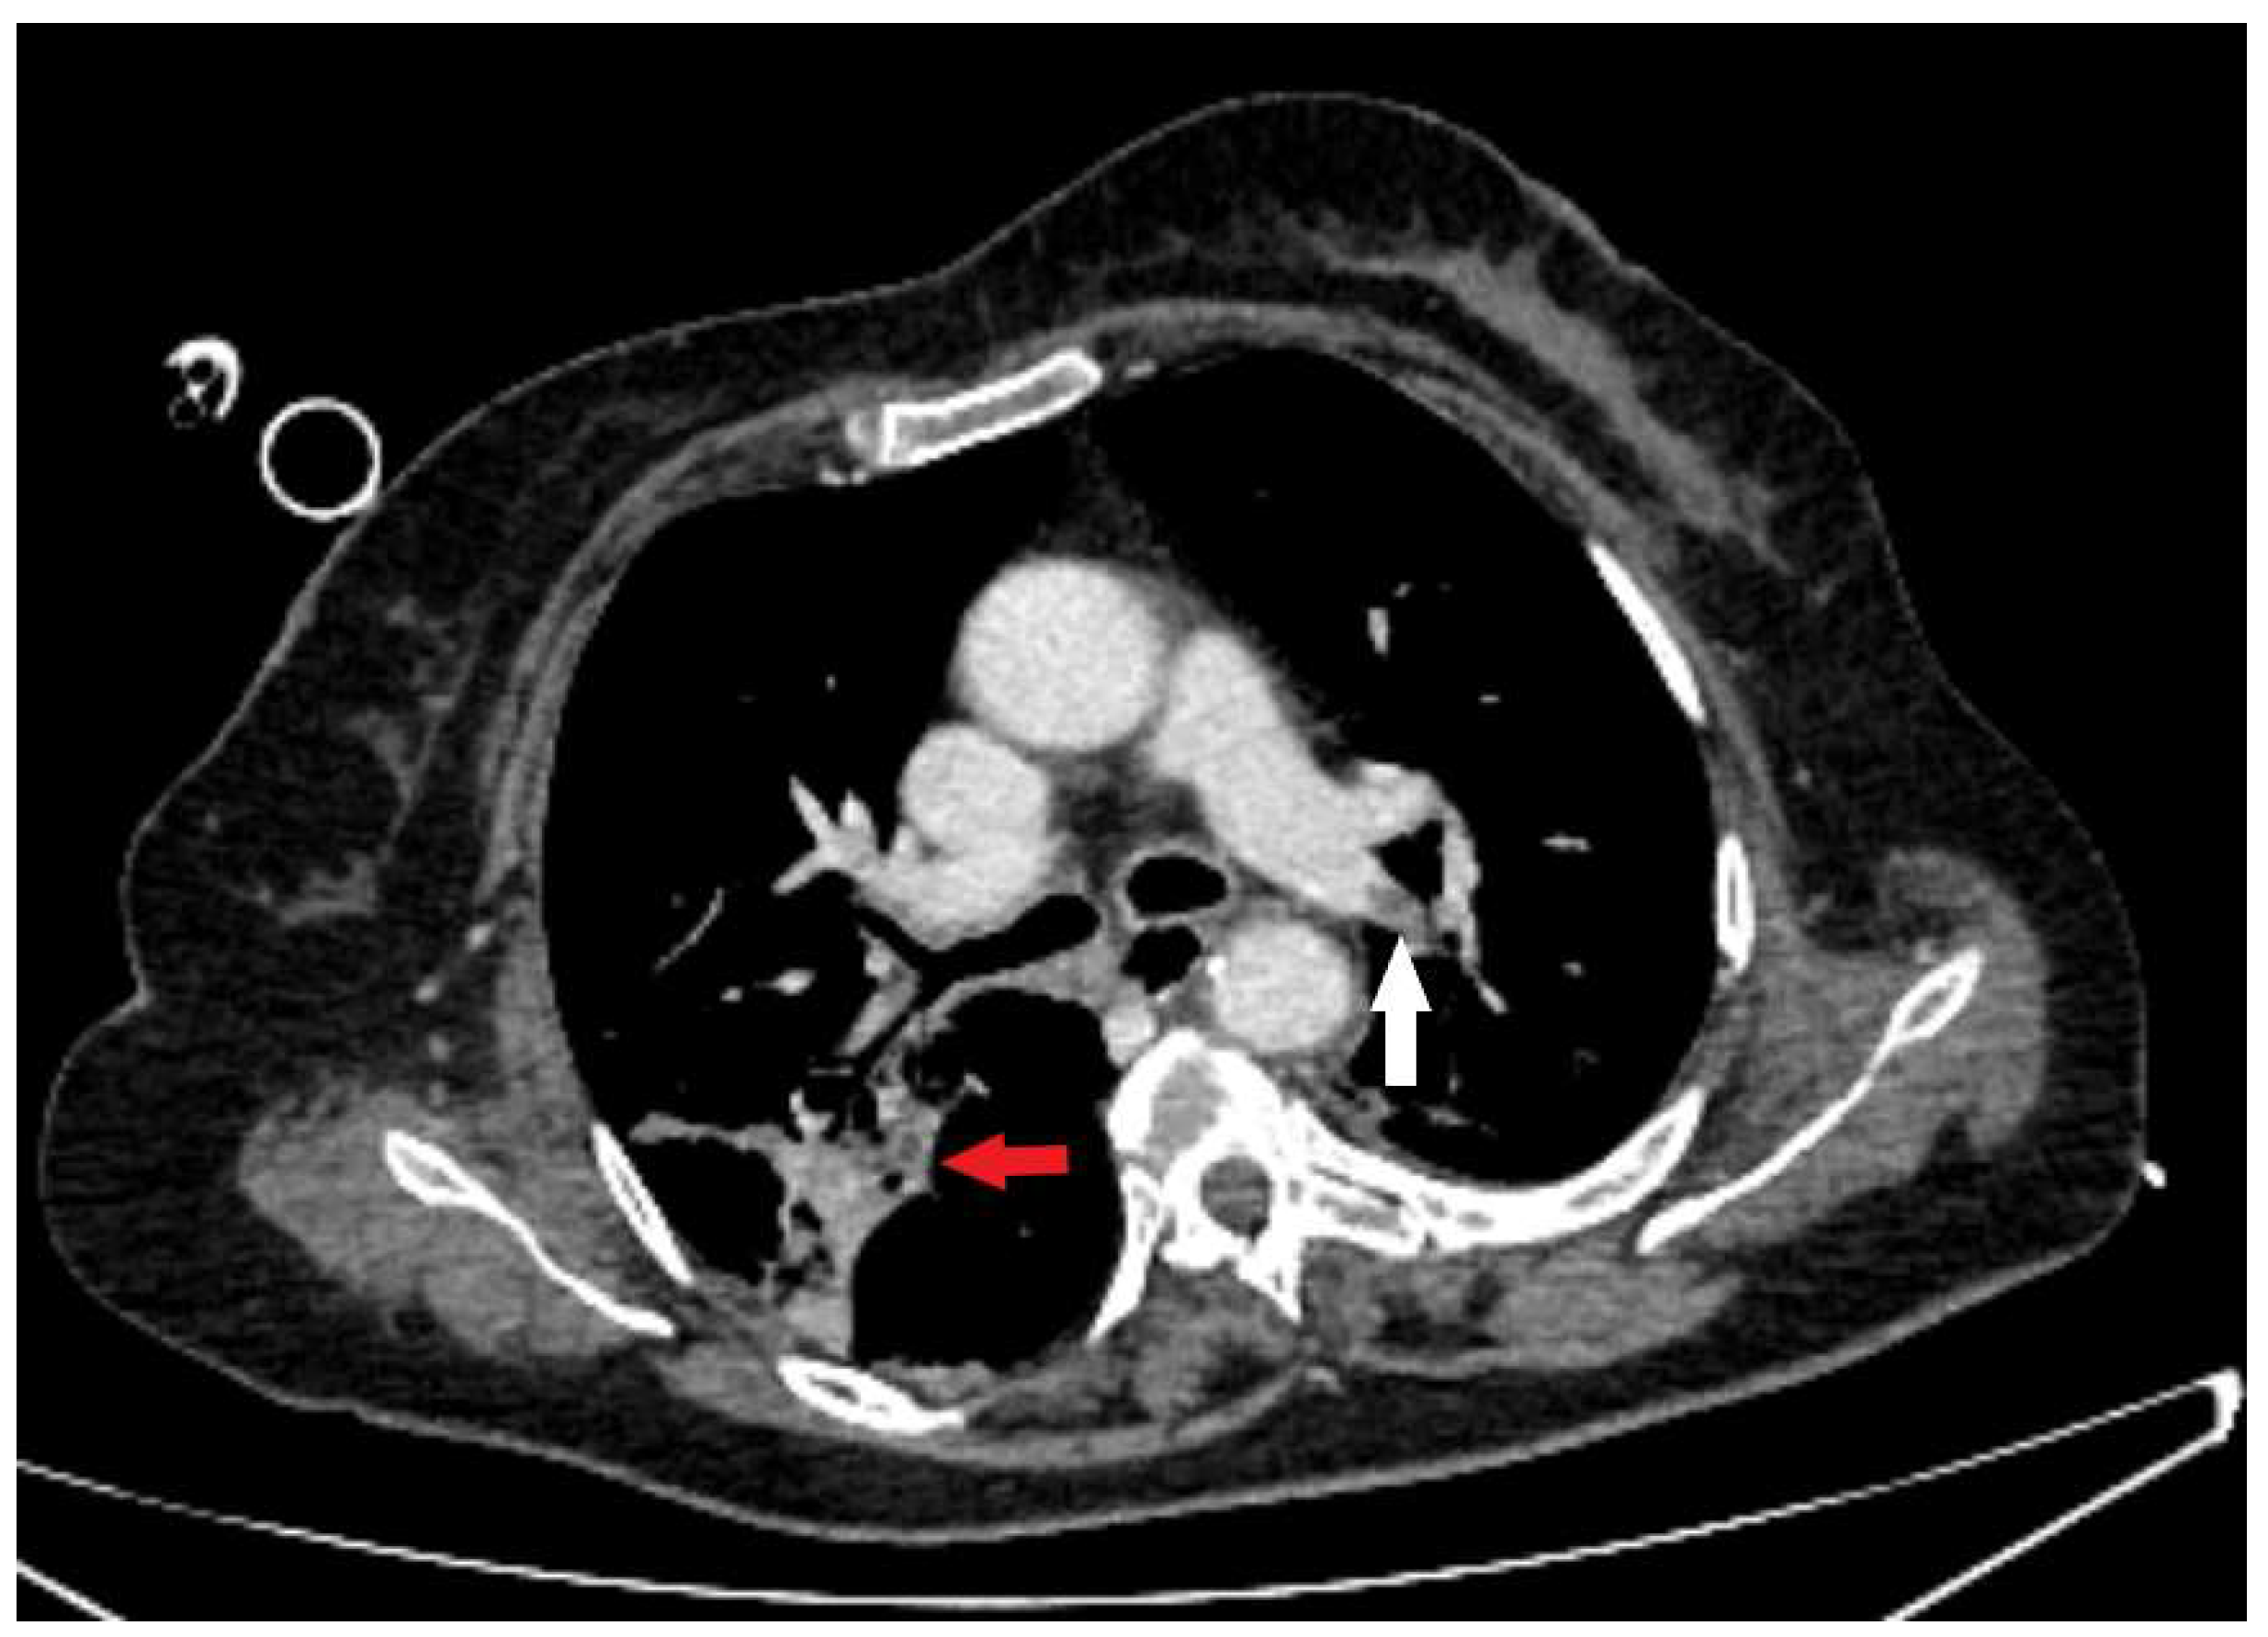

Figure 3. An axial CT scan demonstrates intraluminal defect in the postcontrast opacification of the lobar branch of the left pulmonary artery (white arrow), which corresponds to pulmonary thromboembolism with present consolidative parenchymal zones consistent with aspiration pneumonia (red arrow).